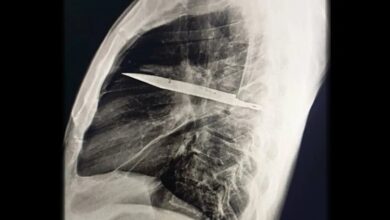

کشف عجیب در قفسه سینه؛ چاقویی که ۸ سال در بدن مردی جا خوش کرده بود/ عکس

به گزارش خبرآنلاین، در یکی از نادرترین موارد پزشکی ثبتشده، مردی ۴۴ ساله اهل تانزانیا با ترشح چرک از قفسه…